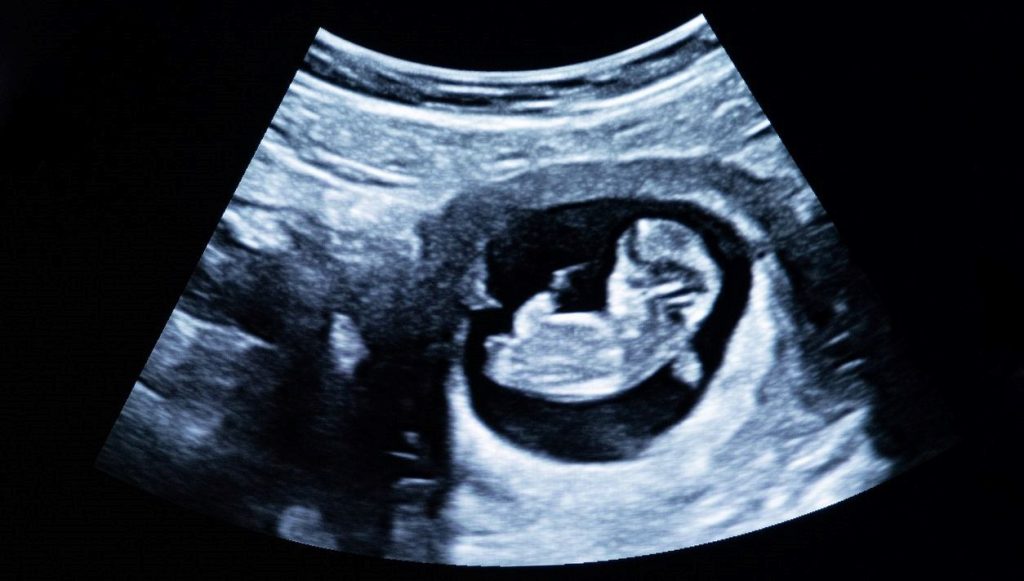

Hindistan’da yaşanan ve az görülen bir tıbbi olay, hekimleri ve bilim dünyasını şaşkına çevirdi.

Yeni doğan bir bebek, kendi karnında gelişen iki fetüsle dünyaya geldi.

Bu, tıp literatüründe “Fetus in fetu” olarak isimlendirilen ve dünyada sırf 200 sefer kaydedilen son derece ender bir anomali.

Kadın, 1 Şubat’ta sağlıklı bir erkek bebek dünyaya getirirken, hekimler gelişimini tamamlayamayan iki fetüsü bebeğin karnından muvaffakiyetle çıkardı.

Taramayı gerçekleştiren Dr. Prasad Agarwal, “Karnında fetüs gibisi bir yapı bulunan, olağan büyüyen bir bebek gördüm. Bu, dünyanın en ender hadiselerinden biri” dedi.

Anne ve bebeğin sıhhat durumunun yeterli olduğu belirtilirken, içeride gelişen öbür iki fetüsün hayatta kalamayacak kadar az gelişmiş olduğu bildirildi.